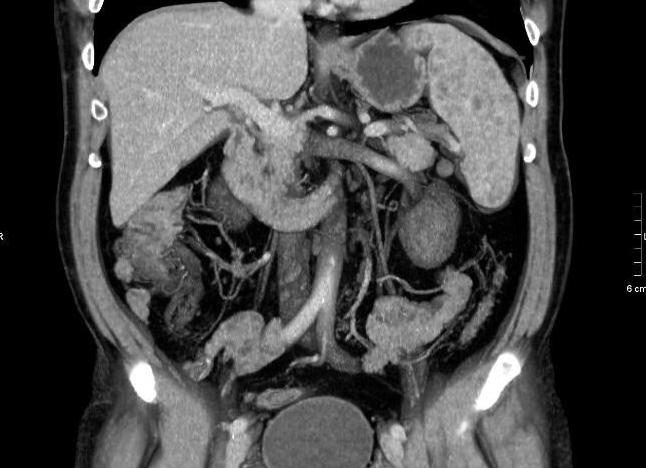

Тканное образование забрюшинного пространства слева. Изображения, полученные во фронтальной проекции, дают возможность оценить взаимоотношение образования с другими органами, рост образования в другие органы и ткани.